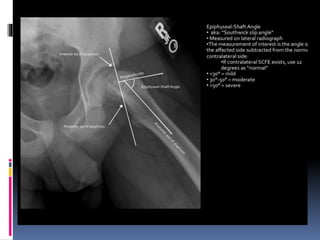

 DEPENDING ON AMOUNT OF DISPLACEMENT:

1. Grade 1 – mild slip – neck displaced <1/3 diameter of head in lat view,

head shaft angle deviates by 30degree on both ap & lat.

2. Grade 2 –moderate slip – neck displaced between 1/3 to ½ , head shaft

angle between 30 to 60 degrees.

3. Grade 3 – severe slip – neck displaced >1/2 , head shaft angle >60

degrees.

 Head shaft angle.

 Angle b/w axis of

femur shaft &

perpendicular to

base of epiphysis.